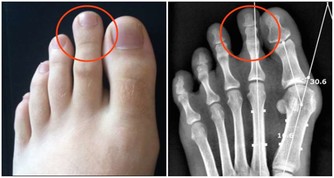

「恐懼」器官——腎臟

腎臟功能下降的話,人稍微遇到一點小異樣便會非常不安,就容易憂心忡忡。對於未知的將來總是過於擔憂的你,很可能是受到驚嚇的腎臟在對你提出抗議呢。腎一虛弱人就易恐懼,越恐懼腎就越虛,結果就是,每天沒精打采,眼睛又酸又澀,腰特別酸,沒幹什麼活兒也覺得非常疲勞,老想睡覺。而且還常常是吸氣時吸不進去,呼氣時使勁嘆氣,我們稱之為「腎不納氣」,是腎虛的癥狀之一。黑色的食物補腎,因此可以多吃黑米、黑豆、黑木耳、海帶、紫葡萄等。而過鹹的食物或是鹽的攝入量過多,會導致腎功能失調,很多尿毒症的患者就是因為攝入了過多的鹽分。